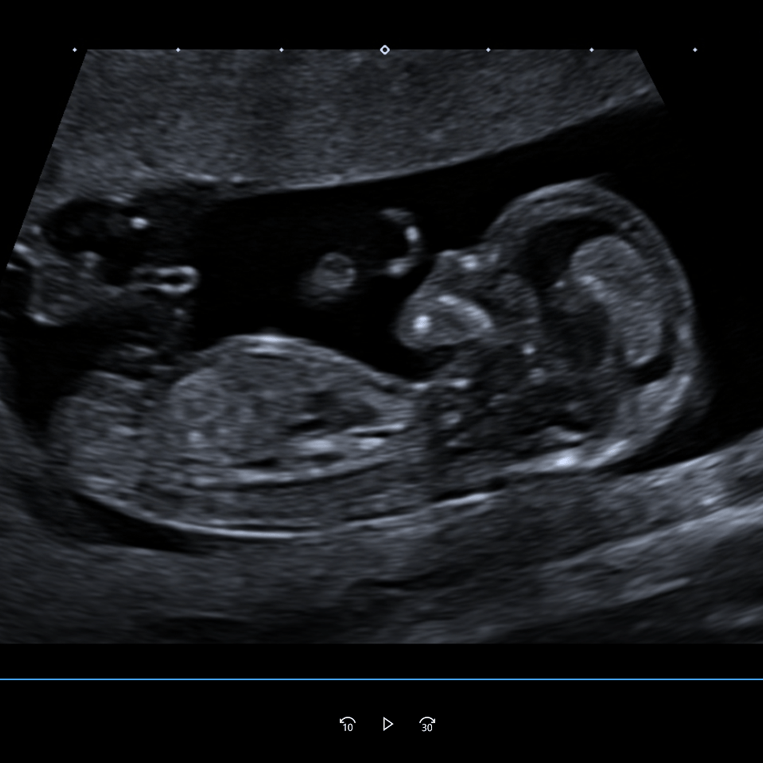

Die eine zusätzliche Pränatale Sprechstunde findet immer dienstags zwischen 14.00 und 18.00 Uhr am AK Nord Heidberg statt. Das ermöglicht eine engere Zusammenarbeit mit dem Kreißsaal und sämtlichen Kollegen des Perinatalzentrum Level 1.

Auch dort gibt es das gesamte Spektrum der vorgeburtlichen Ultraschalldiagnostik. Die Terminvereinbarung erfolgt einfach über die Hauptstelle in Ahrensburg telefonisch oder per E-Mail.

Schwangerschaft

Während der Schwangerschaft treten häufig viele Fragen auf. Daher ist es umso wichtiger, dass Sie sich gut aufgehoben und fundiert beraten fühlen.